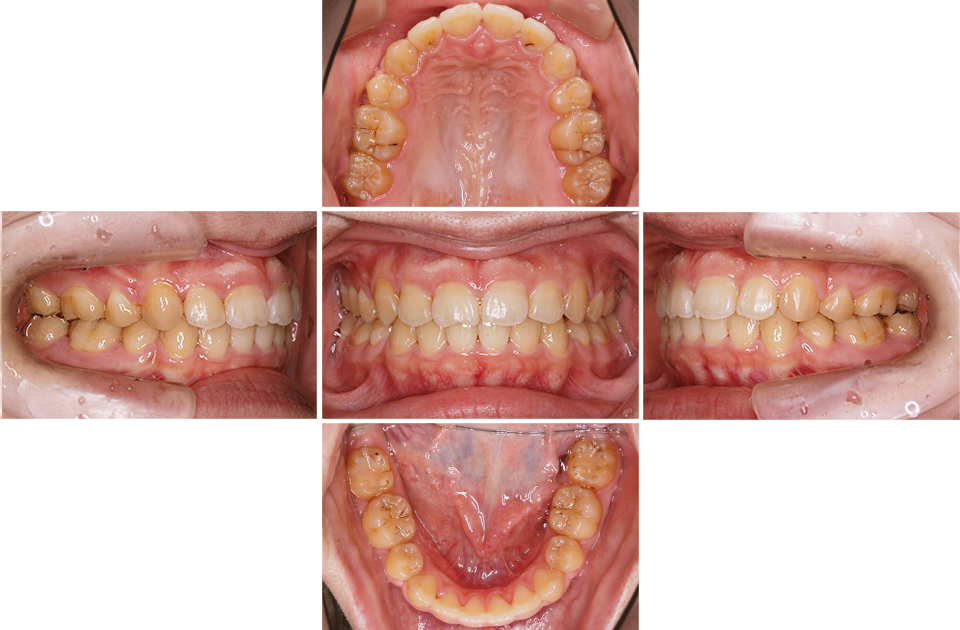

矯正後

矯正後 正面

矯正後 右側

矯正後 左側

矯正後 上顎

矯正後 下顎